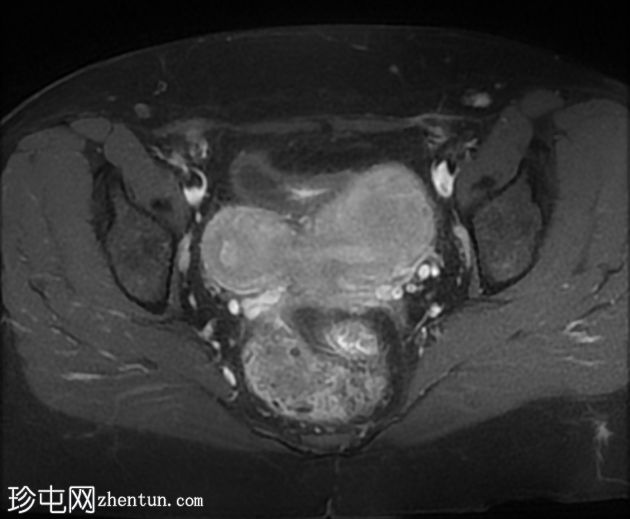

冠状位

STIR序列

双角子宫,有两个子宫角和一个宫颈(单颈双角子宫)

右角正常,分区解剖结构正常,无肌层病变

左角局灶性前壁腺肌症,前壁交界区边界不清,肌层内可见多个高信号灶

两个小的间质性肌瘤和一个大的浆膜下肌瘤

该病例表现为双角子宫单宫颈(双角单颈子宫),左侧单侧局灶性子宫角腺肌症,以及多发性子宫肌瘤。